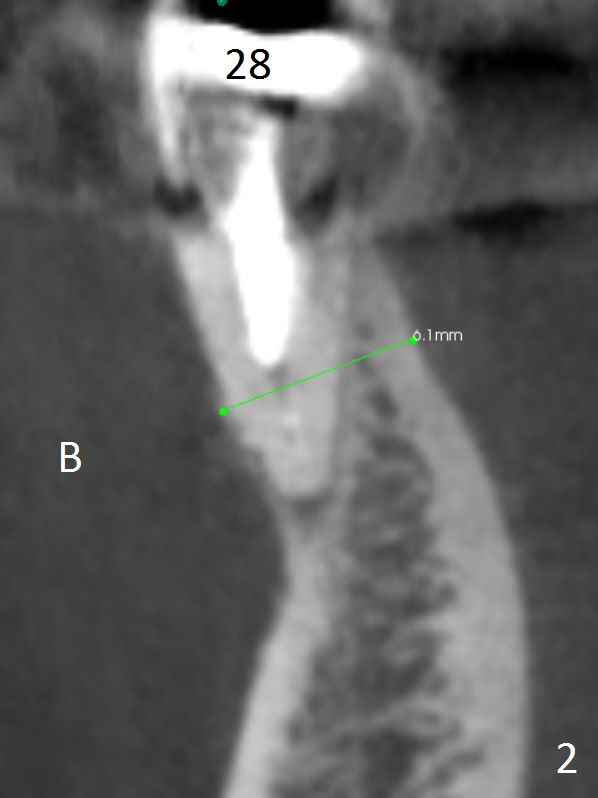

A 64-year-old woman has had sign of periimplantitis at #29 (Fig.1 (CBCT sagittatl section)) in the last 3 years. It appears that the implant is buccally and superficially placed (Fig.3 (coronal section)). Although RCT at #28 is incomplete (Fig.2), there is no symptom or sign of active infection; no treatment will be rendered.